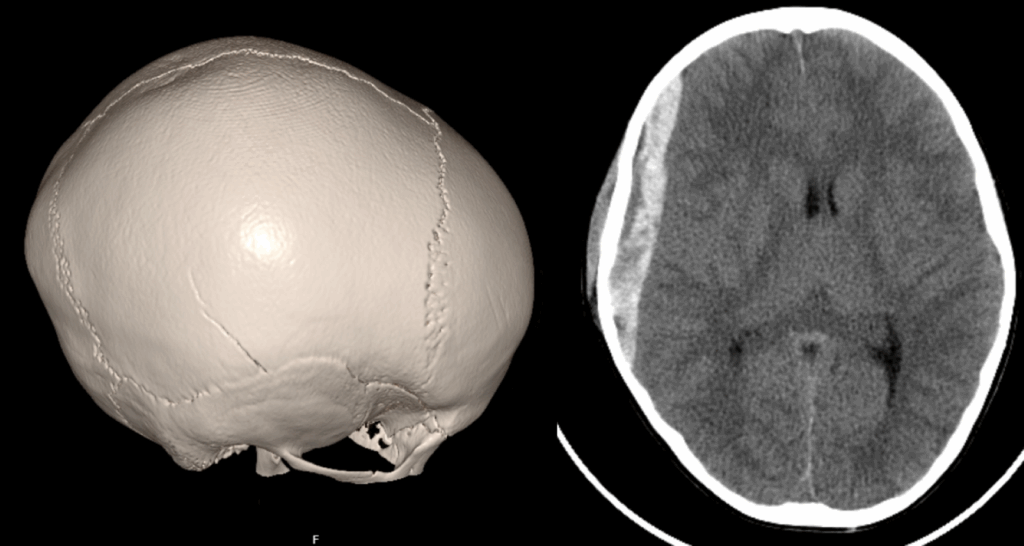

“U posljednjih godinu dana vidjeli smo djecu s ozbiljnim neurokirurškim ozljedama, uključujući slučajeve u kojima se kost pri padu zabila u moždano tkivo. Svaka ozljeda koja poremeti razvoj dječjeg mozga može imati dugotrajne posljedice – od oštećenja sluha i vida do problema s pažnjom, učenjem i ponašanjem”, upozorio je neurokirurg Miroslav Gjurašin.

Epiduralni hematom, FOTO: Klaiceva bolnica